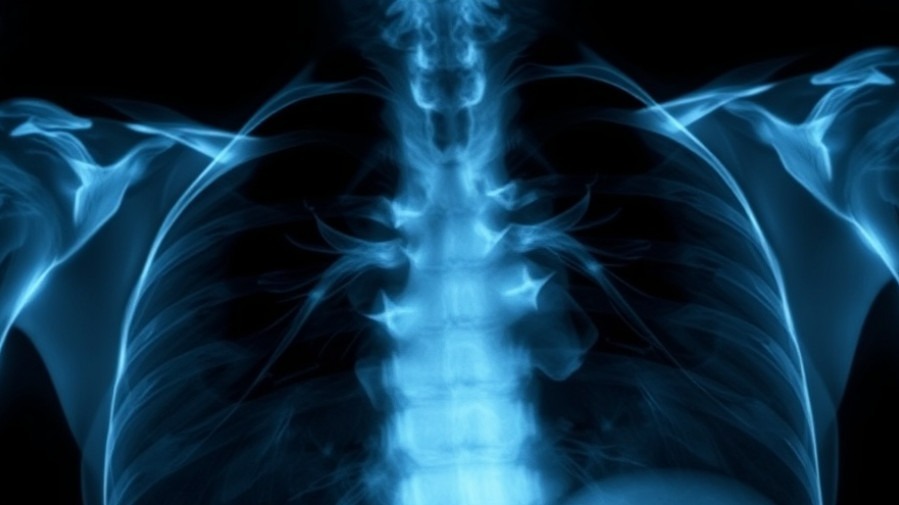

Understanding Esophageal Cancer: An Overview

Esophageal cancer is characterized by the growth of malignant cells in the esophagus, the muscular tube responsible for transporting food from the throat to the stomach. This type of cancer commonly manifests in two forms: squamous cell carcinoma, found primarily in the upper and middle esophagus, and adenocarcinoma, which typically arises in the lower esophagus. Understanding the risks—like smoking and heavy alcohol consumption—and recognizing symptoms such as weight loss, hoarseness, and difficulty swallowing is critical for early detection and treatment.